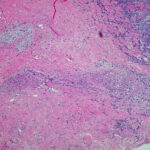

Histopathology . Pyoderma gangrenosum exhibits a dichotomous tissue reaction, showing central necrotizing suppurative inflammation, usually with ulceration, and a peripheral lymphocytic vascular reaction comprising perivascular and intramural lymphocytic infiltrates, usually without fibrin deposition or mural necrosis . Transitional areas show neutrophils in a loose cuff around the angiocentric lymphocytic infiltrates, defining a mixed lymphocytic and neutrophilic vascular reaction termed a Sweet’s-Iike vascular reaction . Bullous lesions may also demonstrate a Sweet’s-like vascular reaction with perivascular disintegrating neutrophilic infiltrates and hemorrhage without mural necrosis or luminal fibrin deposition. At variance with Sweet’s syndrome is destruction of the connective tissue framework with resultant tissue pathergy . Although a leukocytoclastic vasculitis may be observed in areas of maximal tissue pathology, pyoderma gangrenosum does not reflect a primary vasculitis . In some cases a necrotizing pustular follicular reaction may be the central nidus of the lesion, particularly in the vesicular pustular variant associated with ulcerative colitis or hepatobiliary disease. In the superficial granulomatous variant, florid pseudoepitheliomatous hyperplasia may be observed along with the intraepithelial and superficial dermal suppurative granulomatous inflammation with admixed plasma cells and eosinophils . Gases of pyoderma gangrenosum associated with Grohn’s disease may have areas of granulomatous inflammation . |